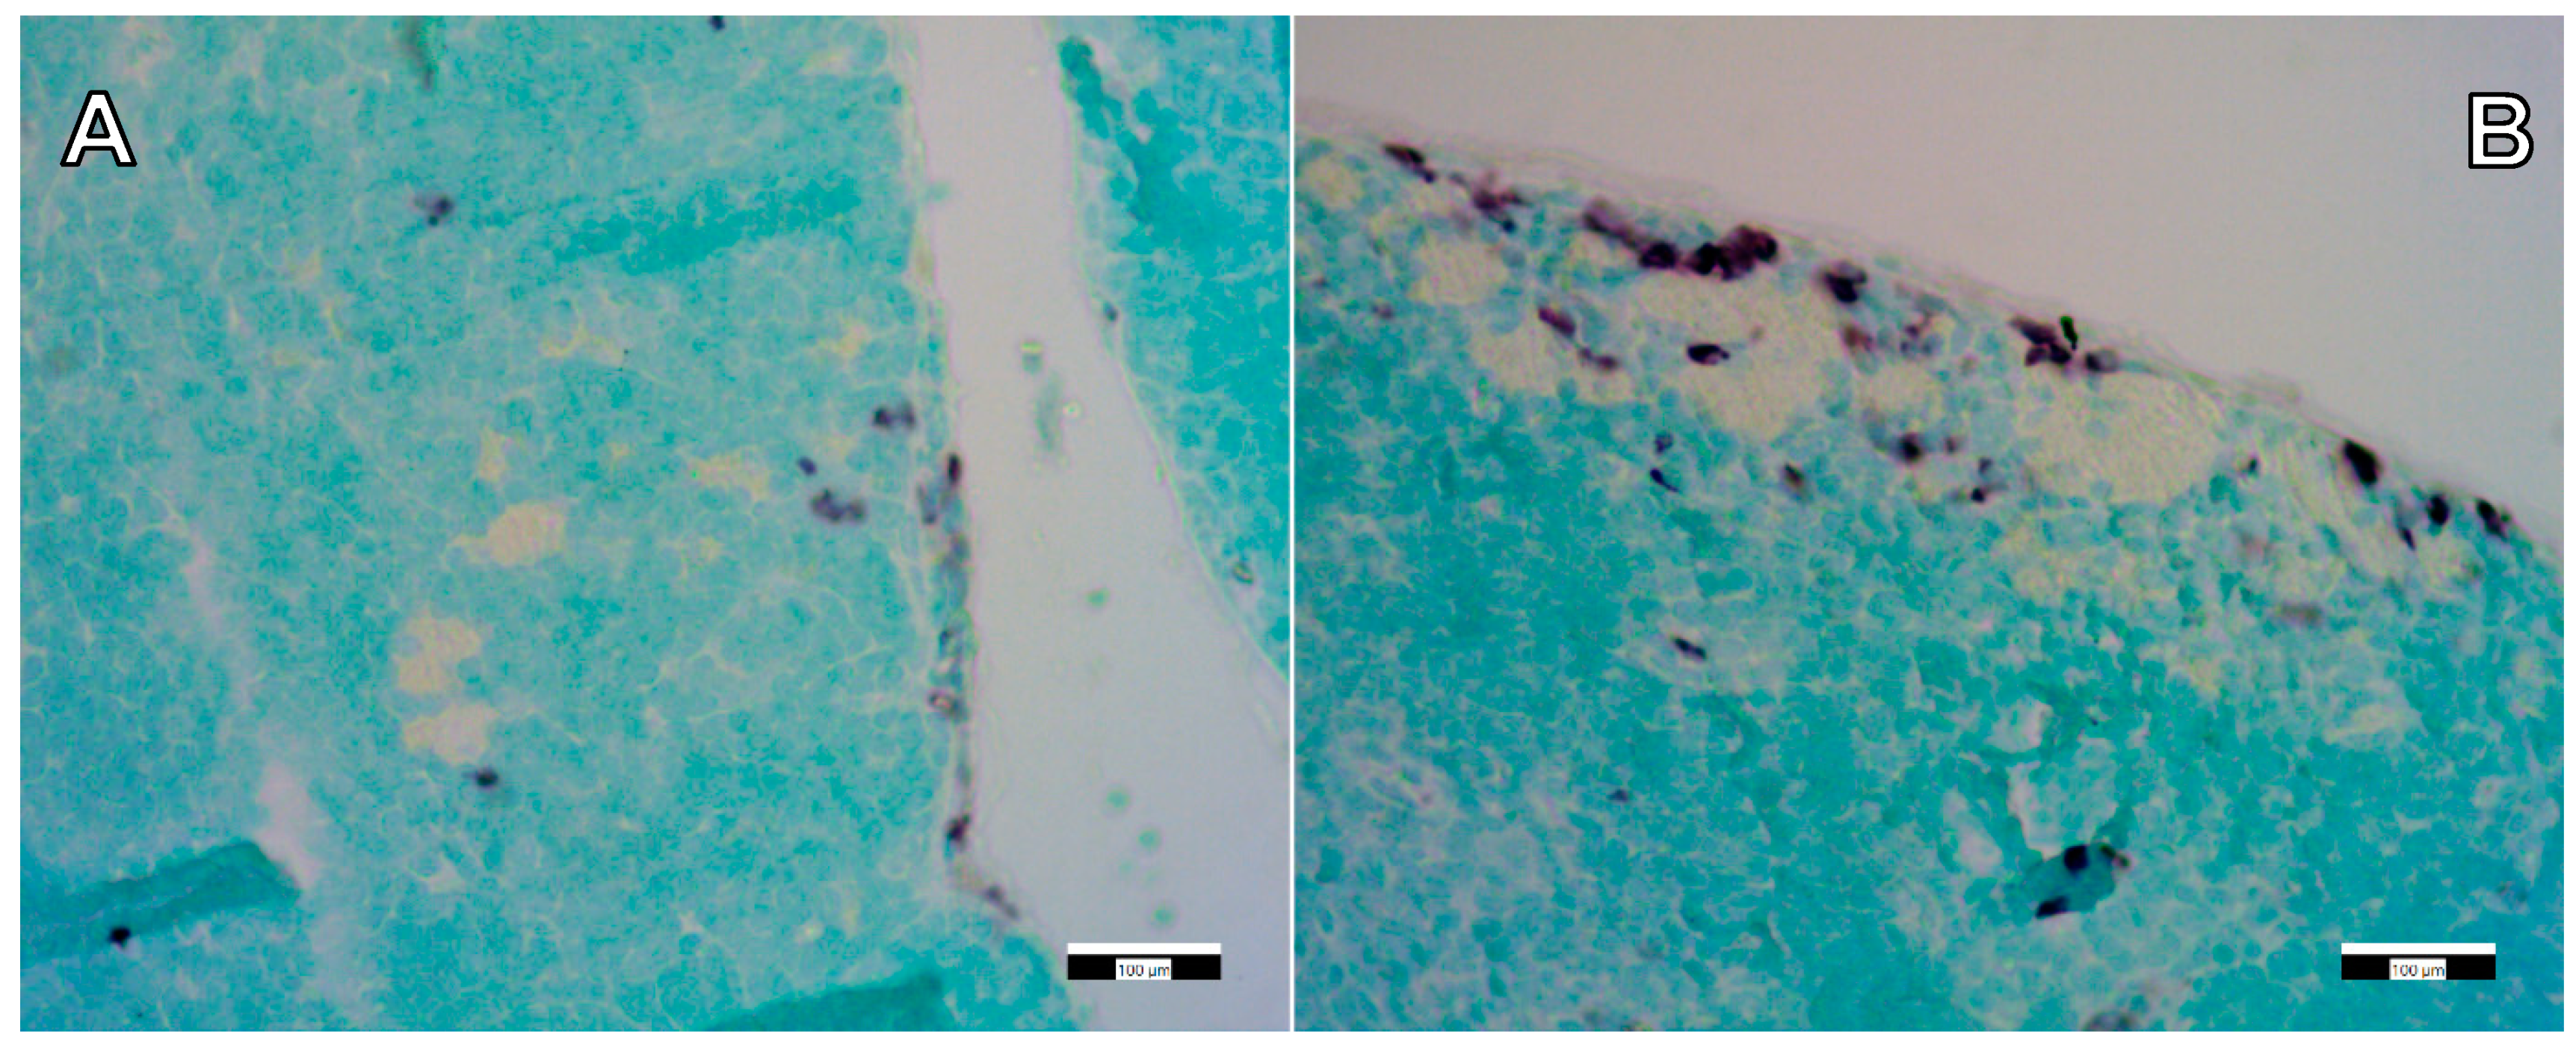

3.2. Biodistribution of Aerogel Microparticles

3.3. Immunohistochemical Staining